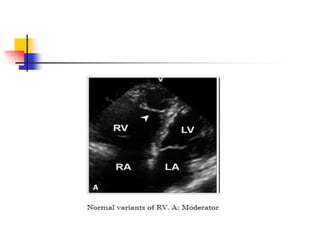

 The moderator band of the right ventricle has been

misinterpreted as an intracardiac mass.

 In echo, moderator band is a thick echo-dense band-

like structure across the RV cavity and connects the

lower interventricular septum and the anterior

papillary muscle

 It is often best seen in the ME four-chamber view

Moderator band  Themoderator band of the right ventricle has been misinterpreted as an intracardiac mass.  In echo, moderator band is a thick echo-dense band- like structure across the RV cavity and connects the lower interventricular septum and the anterior papillary muscle  It is often best seen in the ME four-chamber view